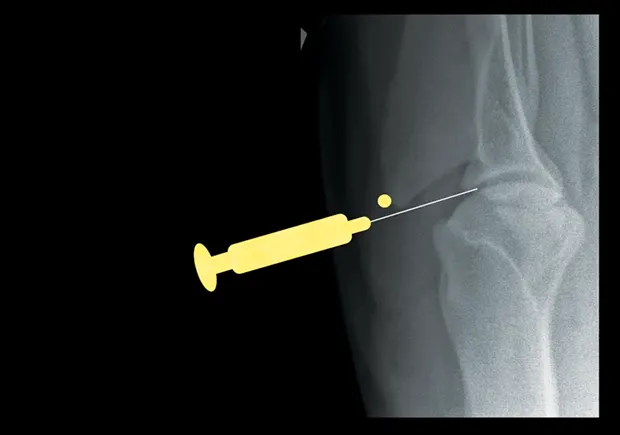

Elbow

With the patient in lateral recumbency and the affected elbow downward, place a rolled towel beneath the elbow. Apply valgus stress on the joint over the towel to open the medial side of the elbow. For large-breed dogs, insert the needle 1.5 cm distal to the medial epicondyle in a medial-to-lateral direction. The caudolateral pouch of the joint is an alternate site; however, marked effusion must be present for successful arthrocentesis.

Craniocaudal view of elbow. Insert needle about 1.5 cm distal to the medial epicondyle (yellow dot) in large-breed dogs.